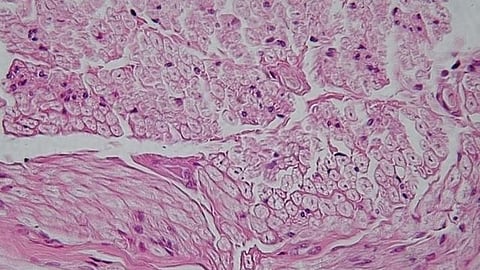

In order to experimentally prove that the squid scaffold is suitable for growing human cells, scientists have placed samples into small plastic nutrient-filled walls, and afterwards applied human stem cell cultures onto their surfaces.

Cell culture observation has shown that in four days the cells strongly bound to the collagen scaffold, forming a big network with each other. Besides that, cells began to actively interact with the substrate, transforming it and releasing extracellular matrix into the environment — molecules which play an important role in tissue restoration. The authors have also concluded that squid collagen has no toxic effect, since the median survival of cells that were cultivated there was 90%.